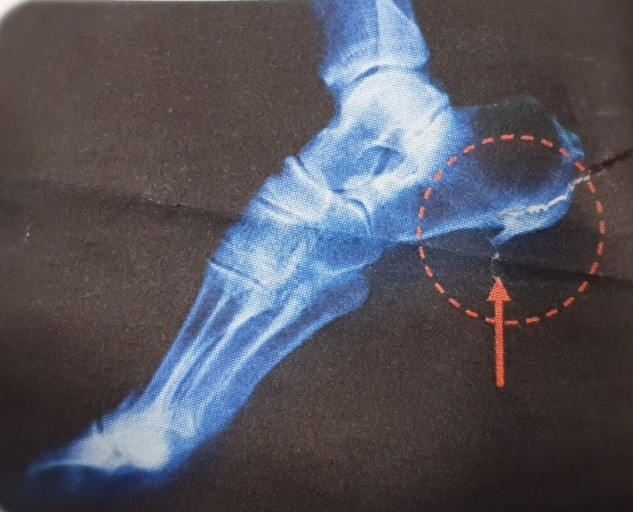

8. 발바닥에 딱딱한 결절

일부 환자들은 발꿈치에 결절이 생길 수 있습니다. 결절은 발꿈치 뼈에 작은 돌출부위로, 족저 근막염이 장기화되면 나타날 수 있습니다. 이 결절은 발꿈치를 눌렀을 때 통증을 유발합니다.